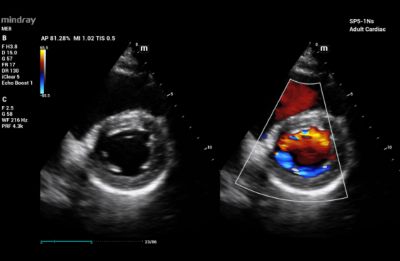

Heart

Echocardiography utilizes a type of CDI that examines the heart and the velocity of blood flow through the cardiac valves and detects any irregularities between the left and right sides of the heart. CDI of the heart can also determine if there is any blood leakage through the valves.

Color Doppler Imaging of Mitral Valve Dehiscence

Color Doppler Imaging of Patent Ductus Arterosus